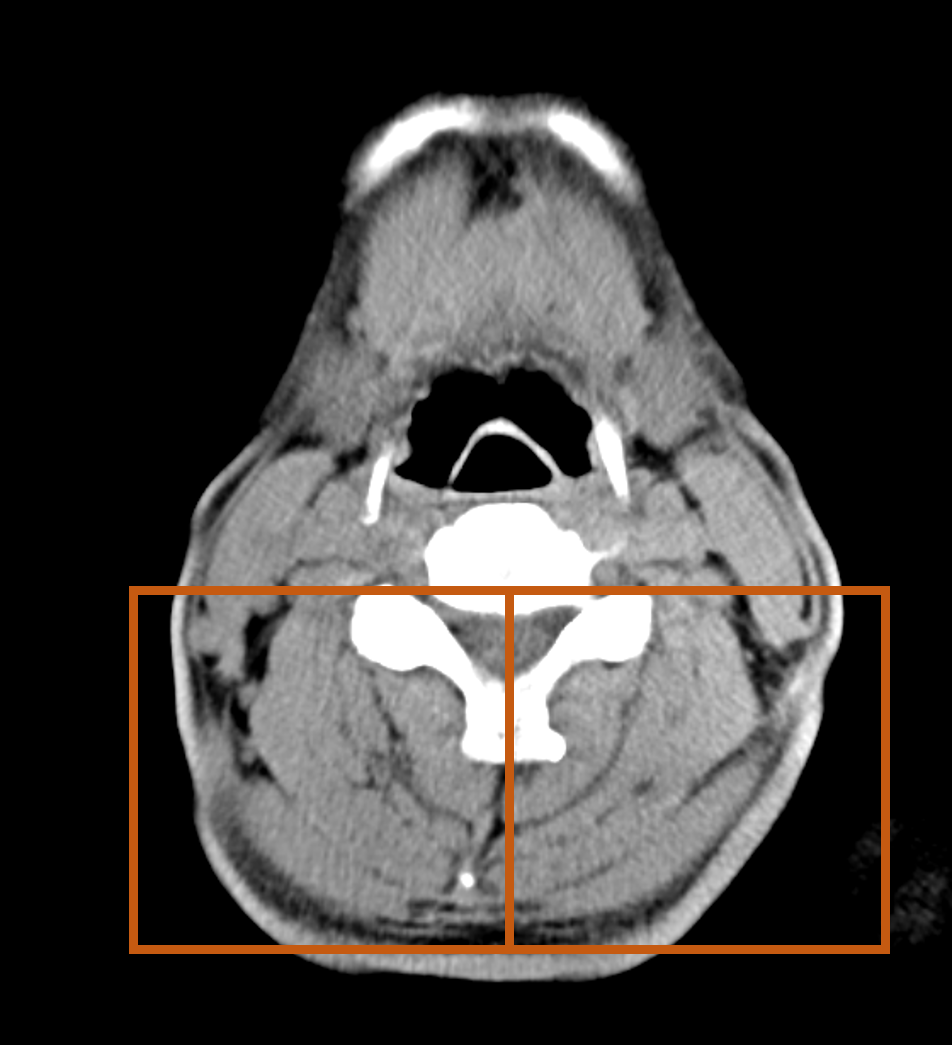

밖에서부터 배를 감싸는

배 바깥 경사근( external abdominal oblique m.)

배속 경사근( internal abdominal oblique m.)

배가로근( transverse abdominis m.)을 합해서 삼겹살이라고 한다. 다시 한번 위치를 확인해 본다.

<검은색이 지방이고, 회색이 근육 아니 살이다>